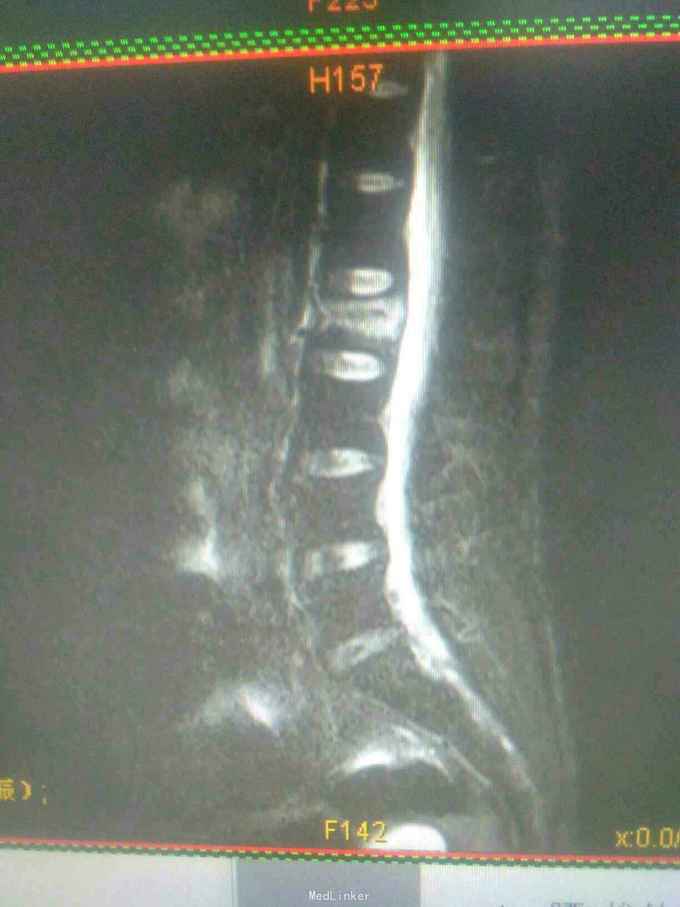

一例腰椎骨折行经皮椎弓根钉内固定术

患者因跌伤致腰背部疼痛,活动受限1小时入院。入院时双下肢活动好,无大小便功能障碍。

查体:腰2椎体棘突压痛明显,双下肢肌力、肌张力正常,腱反射可引出,感觉正常,未引出病理反射。

诊断:腰2椎体压缩性骨折。手术:于插管全麻下行经皮椎弓根钉内固定术。